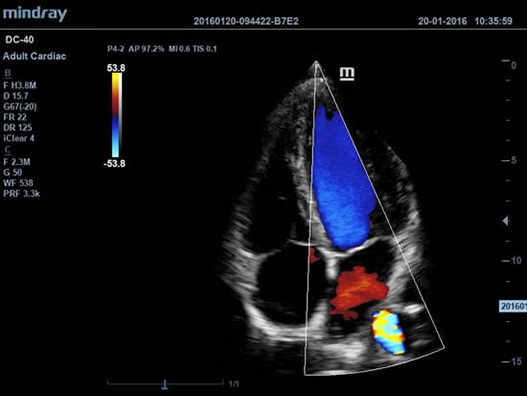

Mindray DC-40 - передовая УЗ-станция с выдающимися возможностями в области медицинской диагностики. Компания Mindray разработала это устройство с учетом высоких требований врачей к качеству изображения и быстродействию. DC-40 обеспечивает высокое качество изображения и точность диагностики, что является необходимым в повседневной практике врачей. Технологии, применяемые в этом устройстве, позволяют получать четкое и детализированное изображение.

Технологии iBeam, iClear и iScape, применяемые в DC-40, позволяют получать объемные изображения высокого качества без помех и зернистости в зоне сигнала. Панорамная визуализация с расширенным обзором анатомических структур решает проблемы сложных диагнозов, которые ранее создавали значительные трудности в ультразвуковой диагностике.

DC-40 имеет особое применение в кардиологической практике, благодаря функции Free Xros CM. Она позволяет отслеживать движения сердечной мышцы в различных фазах и одновременно определять синхронизацию миокарда. Это существенно повышает точность диагноза.

• Секторный фазированный датчик Mindray P4-2